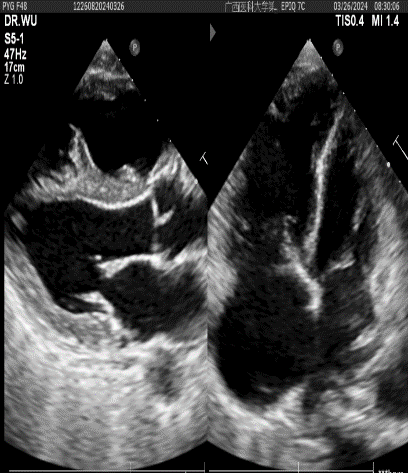

▲术前心脏彩超:右房室增大+三尖瓣、肺动脉瓣轻度关闭不全+肺动脉主干及分支增宽